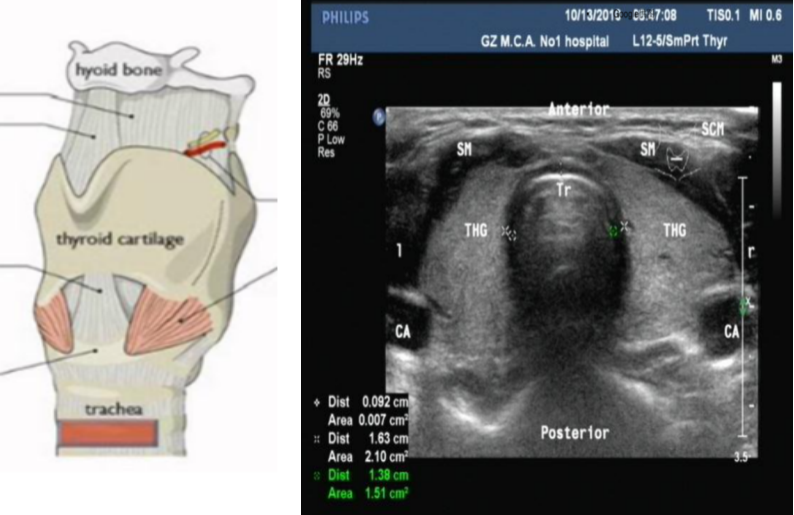

超声可以帮助预测气管内径和支气管内径,且用于选择儿童的气管插管型号比成年人更有意义。儿童传统气管插管的选择往往根据公式计算而来,而现在的儿童发育生长变异都比较大,无论根据年龄(气管插管内径=4+年龄/4)还是体重的选择,误差都比较大。超声的气管直径检查和CT检查一致性很好。此时选择在超声下测量声门下气管的内径,再选择相应的气管插管,针对性更好。相关研究也提示其准确性已达到88%。对成人而言,CT检查提示的主气管外直径与左主支气管内径之比为0.68。我们通过超声在胸锁关节测量气管直径,对选择双腔气管插管(左主支气管)的大小也是有用的。图15为通过超声来确定气管插管大小的实时演示图。

图片

图15  超声在气管软骨环横平面横向查扫

注:右图测量的双绿色测量点为气管的直径1.51 cm,半径7.5 mm。